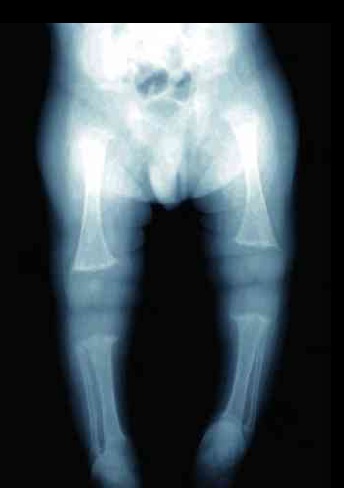

Raşitizm, bu kemik hastalığının en belirgin nedeni, D vitamini eksikliğidir. Bunun sebebi de D vitaminin dışarıdan alınmaması yada güneşe çıkmamasıdır. Ama aynı zamanda vücutta D vitaminin çeşitli emildiği yerler vardır, böbrek yada bağırsaklar, böbreklerde yada bağırsaklarda oluşan rahatsızlıklardan dolayı bir takım farklı raşitizm örnekleri ortaya çıkabilir. Anne sütü için bebeklere D vitamini takviye edilmezse D vitamini eksikliği gelişebilir.

Osteomalazi, bu hastalığın en belirgin özelliği yetişkinlerde görülen kemik ağrılarıdır. Bu ağrılar daha çok uzun kemiklerde ve leğen kemiklerinde görülür. Bu hastalığın sebebi D vitamini yetersizliğidir.